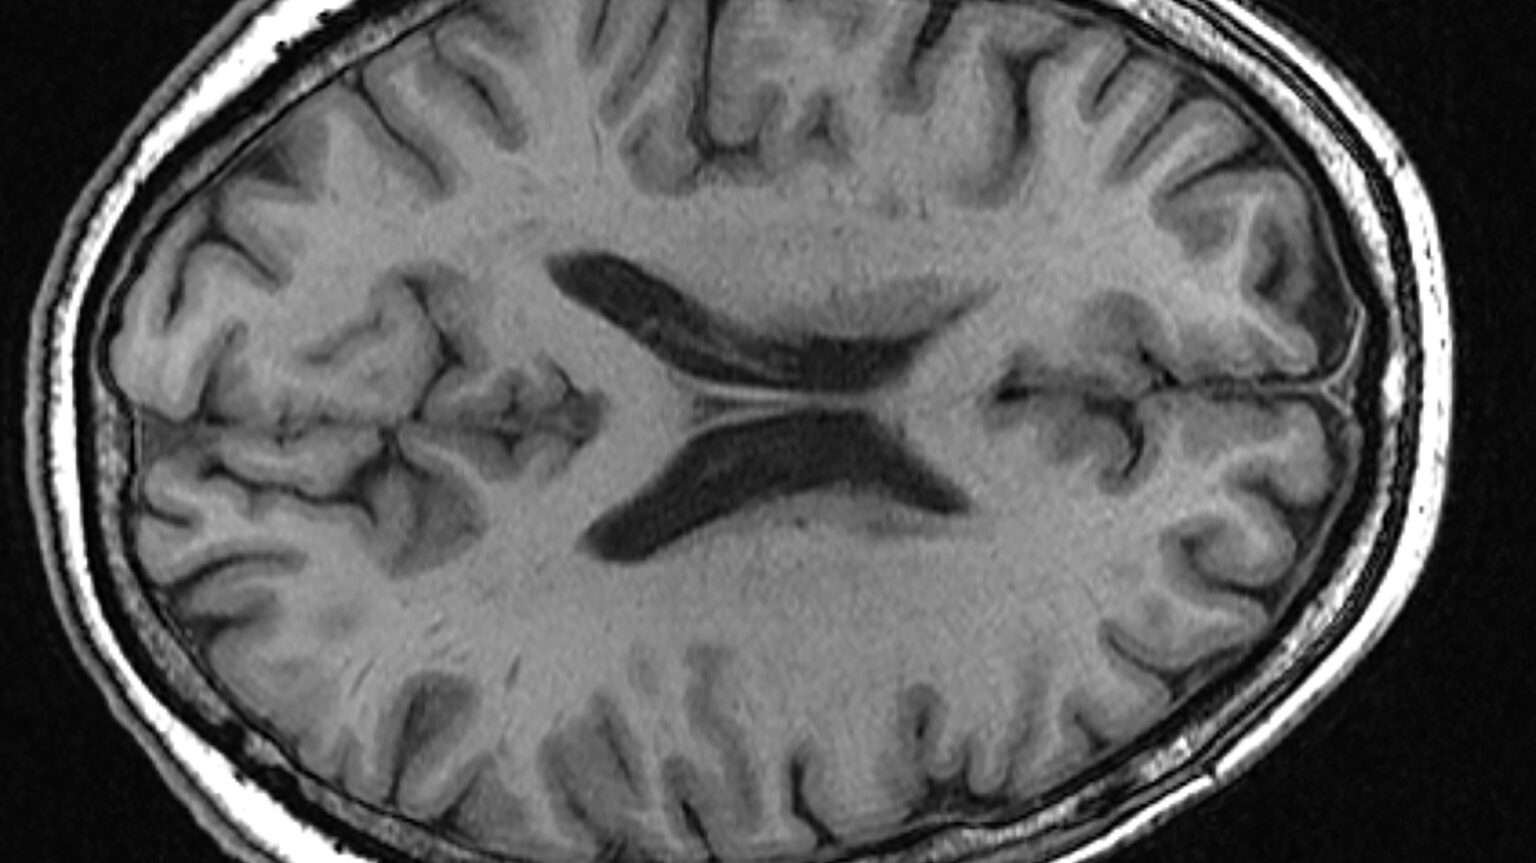

Parkinson’s disease, a debilitating progressive disorder affecting the nervous system, impacts millions worldwide. According to the Parkinson’s Foundation, nearly one million Americans will be living with Parkinson’s by 2020. The disease primarily attacks dopamine-producing neurons, leading to tremors, rigidity, and difficulty with movement. Scientists have increasingly focused on the role of DNA damage accumulation as a crucial factor in the progress and progression of Parkinson’s, particularly with aging.

Parkinson’s disease is characterized by a gradual loss of dopamine-producing neurons in the brain. While the exact cause remains unknown, it is indeed believed to involve a combination of genetic and environmental factors. Beyond motor symptoms, Parkinson’s can also manifest in non-motor symptoms like sleep disorders, depression, and cognitive impairment.